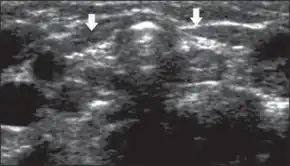

Ultrasonography thyroid gland arrows reduced dimensions, as well as increased echogenicity

In the developed world, nearly all cases of congenital hypothyroidism are detected by the newborn screening program. These are based on measurement of TSH or thyroxine (T4) on the second or third day of life (Heel prick).[11]